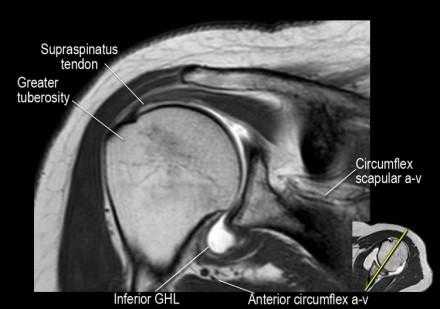

Изображение задних отделов плечевого сустава.

Отображены надостная, подостная и малая круглая мышцы и их сухожилия. Все они прикрепляются к большому бугорку плечевой кости. Сухожилия и мышцы манжеты вращателей участвуют в стабилизации плечевого сустава во время движения. Без манжеты вращателей головка плечевой кости частично сместилась бы из суставной впадины, уменьшив силу отведения дельтовидной мышцы (мышцы вращательной манжеты координирует усилия дельтовидной мышцы). Повреждение манжеты вращателей может привести к смещению головки плечевой кости кверху, в результате вызвая высокое стояние головки плечевой кости.